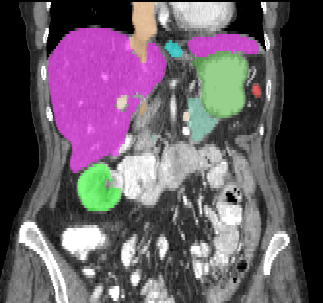

Recently, deep learning methods have achieved state-of-the-art performance in many medical image segmentation tasks. Many of these are based on convolutional neural networks (CNNs). For such methods, the encoder is the key part for global and local information extraction from input images; the extracted features are then passed to the decoder for predicting the segmentations. In contrast, several recent works show a superior performance with the use of transformers, which can better model long-range spatial dependencies and capture low-level details. However, transformer as sole encoder underperforms for some tasks where it cannot efficiently replace the convolution based encoder. In this paper, we propose a model with double encoders for 3D biomedical image segmentation. Our model is a U-shaped CNN augmented with an independent transformer encoder. We fuse the information from the convolutional encoder and the transformer, and pass it to the decoder to obtain the results. We evaluate our methods on three public datasets from three different challenges: BTCV, MoDA and Decathlon. Compared to the state-of-the-art models with and without transformers on each task, our proposed method obtains higher Dice scores across the board.